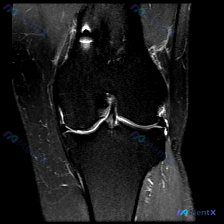

刚整理了一份很有代表性的膝关节影像病例,临床核心问题是询问「软骨异常」的影像学发现,分享一下我的分析思路。 病例基本信息 核心问题:临床疑诊膝关节软骨异常,提供单张膝关节冠状位T1加权MRI影像供分析。 影像所见 1. 骨骼结构:股骨远端、胫骨近端、腓骨近端骨皮质完整,无骨质破坏/断裂,股骨髁与胫骨...